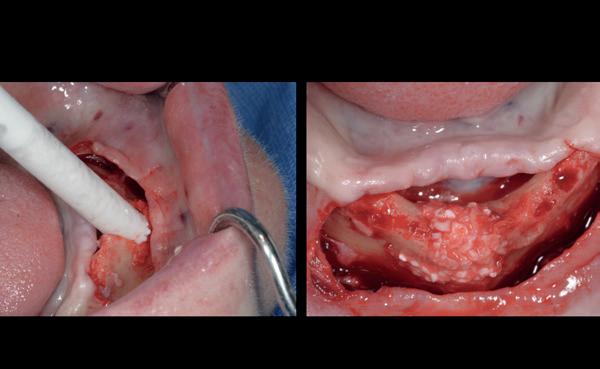

Het kantelpunt: de patiënt komt terug (afbeelding 14-16)

De patiënt meldde zich opnieuw in de praktijk met klachten: pijn, zwelling en een duidelijke intraorale infectie. Bij inspectie zag ik direct een probleemhet ging om een klassiek beeld van peri-implantair botverlies met een abces. Dit patroon van botverlies en infectie spiegelde sterk de gevolgen van thermische trauma.

Op de röntgenfoto’s zag ik wat ik al vreesde: er was botresorptie rond het implantaat. De zachte weefsels waren ontstoken en het implantaat vertoonde teke-

nen van mobiliteit. Op dat moment wist ik precies wat er was misgegaan.

Dit was geen kwestie van een verkeerde occlusie of een slecht gekozen abutment. Dit was een puur biologisch probleem, veroorzaakt door mijn onderpreparatie van de osteotomie en de daarmee gepaard gaande botnecrose of compressie. Mijn streven naar immediaat belasten had me verblind, en ik had een fundamentele regel van de implantologie genegeerd: bot moet kunnen ademen. Op dat moment had ik geen andere keuze dan de situatie te herstellen.

Herstel: terug naar de basis (afbeelding 17-19)

De behandeling van dit mislukte implantaat volgde een stapsgewijze aanpak:

1. Explantatie van het implantaat. Het implantaat werd voorzichtig verwijderd, waarbij ik probeerde zoveel mogelijk bot te behouden.

2. Curettage en reiniging. De alveole werd intensief gecuretteerd en gespoeld tot er geen exsudaat meer aanwezig was. Met goede communicatie kon ik de patiënt overtuigen om 3 maanden later terug te komen voor de botopbouw, zodat we het beste fundament konden creëren voor een duurzame oplossing.

3. Botopbouw met GBR. Ik koos voor een combinatie van allograft, xenograft en autograft om de botdeficiëntie aan te pakken. Dit mixen van bottypes creëerde een optimale omgeving voor regeneratie.

4. Twee-fasen implantologie. Dit keer nam ik geen risico’s. In plaats van een immediaat implantaat koos ik voor een delayed plaatsing. Het bot kreeg eerst de tijd om te rijpen voordat ik een nieuw implantaat plaatste. Deze keer verliep de procedure zonder problemen. Het bot herstelde zich zoals verwacht en na enkele maanden kon ik een nieuw implantaat plaatsen, met een correcte osteotomie en zonder onnodige compressie.